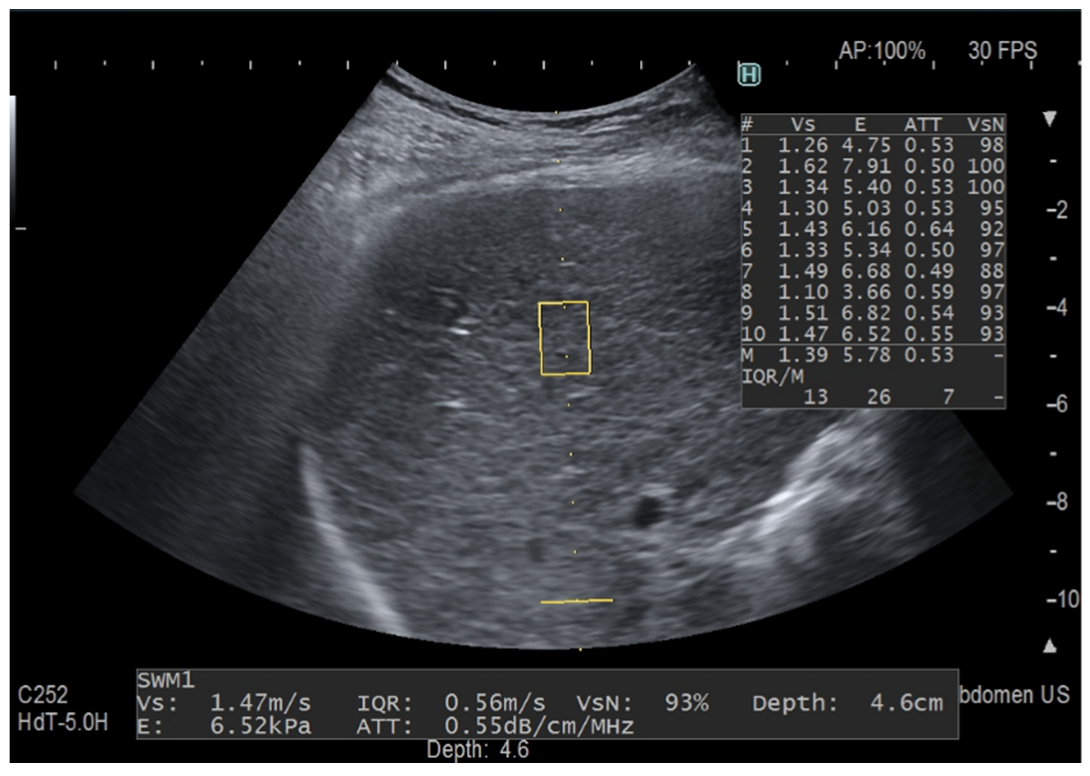

Figure 1.

Fat quantification with the previous ATT algorithm. The yellow rectangle is the region of interest (ROI) for stiffness measurement and the yellow horizontal line indicates the depth of the ATT measurement area in the far field, which is set at 100 mm. The ATT measurement area has a fixed size and the measurement of the attenuation coefficient is given in dB/cm/MHz together with liver stiffness measurement, which is shown both in m/s and kPa. ATT quantifies liver fat content in an areathat has a length of 6 cm and is set at 40–100 mm from the skin. This measurement was taken in a 64-year-old patient with chronic hepatitis C following the protocol for liver stiffness measurement and with a VsN always ≥50%. The attenuation coefficient value is within the normal range.